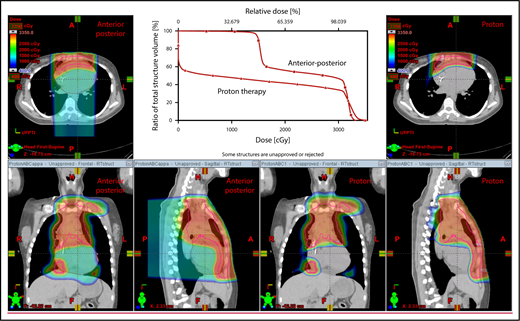

An example of an approach using 2 anterior fields with proton therapy, which can better spare the heart and esophagus (right) compared with an anterior/posterior approach (left).

The plan target is the CTV; when the treatment area is affected by breathing motion, the plan target is the internal target volume (ITV), which encompasses the motion of the CTV depicted on 4D CT scans. Alternately, if treatment is to be given with DIBH, an ITV can be derived from the positions of the CTV reproduced from multiple DIBH scans. For lateral beam shaping, margin expansion to form the PTV accounts for setup uncertainty, and interfractional variability in anatomy is applied to the CTV/ITV. Patient-specific beam collimators conform the dose laterally to the PTV, with a margin for penumbra. Depending on the target depth and adjacent tissue, these margins vary from 5 to 10 mm. Range compensators are designed for each beam to conform the dose distally to the CTV/ITV. Range compensator smearing within a radius appropriate for setup tolerances and tissue motion is applied to account for proton range changes caused by density changes in the beam path. In addition, along each beam, distal and proximal margins are set to the CTV/ITV to compensate for proton range uncertainties, as described under “Range uncertainties due to density variations.” Multiple beams (compared with 1 beam) can be used to increase dose conformality and reduce dose uncertainties by spreading the beams in various directions. The preference is to use anterior or posterior fields, rather than both, because of the need to avoid unnecessary beam through the heart (Figure 4).

Plans for PBSPT with a single-field uniform dose and a gradient match, with anterior and posterior beams used to treat disease that involves the bilateral upper neck and the mediastinum (disease anterior to the right heart).